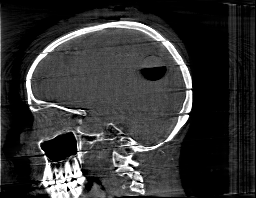

Krylov subspace methods are a powerful family of iterative solvers for linear systems of equations, which are commonly used for inverse problems due to their intrinsic regularization properties. Moreover, these methods are naturally suited to solve large-scale problems, as they only require matrix-vector products with the system matrix (and its adjoint) to compute approximate solutions, and they display a very fast convergence. Even if this class of methods has been widely researched and studied in the numerical linear algebra community, its use in applied medical physics and applied engineering is still very limited. e.g. in realistic large-scale Computed Tomography (CT) problems, and more specifically in Cone Beam CT (CBCT). This work attempts to breach this gap by providing a general framework for the most relevant Krylov subspace methods applied to 3D CT problems, including the most well-known Krylov solvers for non-square systems (CGLS, LSQR, LSMR), possibly in combination with Tikhonov regularization, and methods that incorporate total variation (TV) regularization. This is provided within an open source framework: the Tomographic Iterative GPU-based Reconstruction (TIGRE) toolbox, with the idea of promoting accessibility and reproducibility of the results for the algorithms presented. Finally, numerical results in synthetic and real-world 3D CT applications (medical CBCT and {\mu}-CT datasets) are provided to showcase and compare the different Krylov subspace methods presented in the paper, as well as their suitability for different kinds of problems.